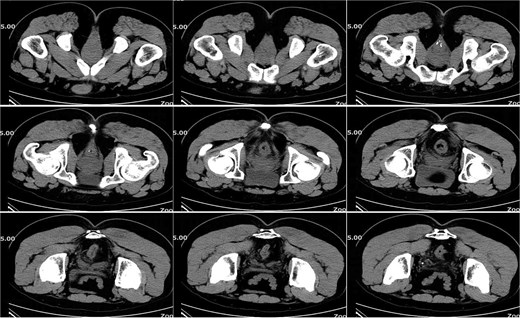

On postoperative Day 10, a repeat complete blood count showed a white blood cell count of 9.74 × 109/l and a neutrophil percentage of 69.5%. The patient’s temperature ranged between 36.4 and 37.4°C, and abdominal discomfort was partially alleviated. A follow-up pelvic CT scan revealed a breach in the anterior rectal wall with gas density shadows communicating with the surrounding area, accompanied by filamentous exudate density shadows and multiple gas density shadows (Fig. 2). These findings indicated rectal wall edema and anterior wall perforation with surrounding infection. Anorectal examination revealed a 0.5 × 0.5 cm ulcerative lesion at the 5 o’clock position of the anastomosis site in the knee–chest position. This was considered rectal perforation secondary to anastomotic dehiscence. Given the absence of peritoneal irritation signs and normalization of the white blood cell count, a conservative treatment plan was adopted after discussion with the patient. This plan involved continuing anti-infective treatment with intravenous cefoperazone sodium and sulbactam sodium.